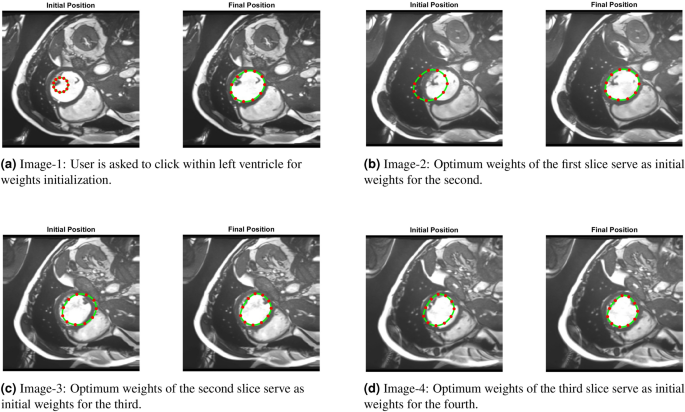

-

3D PICS procedure: Figure 15 demonstrates the 3D segmentation process of the left ventricle in the PICS framework. The initialization process begins with a single click within the left ventricle on the first MRI image. Subsequently, the optimal PIC weights obtained from the previous image are transferred as the initial condition for the next image. The transfer learning accelerates the convergence of the PIC to its optimal value. This iterative process is continued for all the remaining images.

Speed up: Figure 16 illustrates an example of the speed-up in convergence due to this transfer learning process. Usually, the initial segmentation is finished in less than 30 s, while all the remaining segmentations also typically conclude within 30 s. Therefore, the full 3D segmentation takes about a minute to complete.